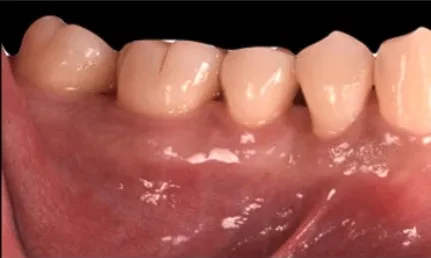

Face externe

Des techniques chirurgicales de préservation papillaire permettent de régénérer les tissus parodontaux en garantissant leur maintien esthétique. Ces techniques chirurgicales avancées s’effectuent sous aides optiques grossissantes et avec des instruments micro chirurgicaux spécifiques.

Avant l’intervention

Quelques semaines après l’intervention